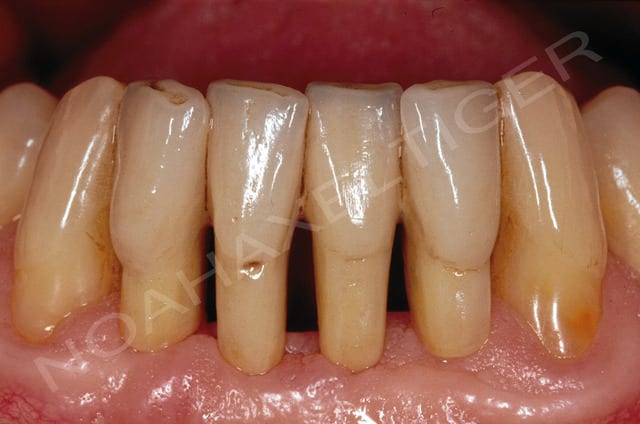

la patiente a 27 ans, elle aperdu ces 4 incisives mandibulaires il ya plusieurs années dans un accident.

La crête osseuse est ultra résorbée et très fine.

Elle vient me voir (si si) et me demande si je peux lui poser des implants sans greffe.

mon idée c'est que c'est possible, et vous vous le feriez? et quelle prothèse?